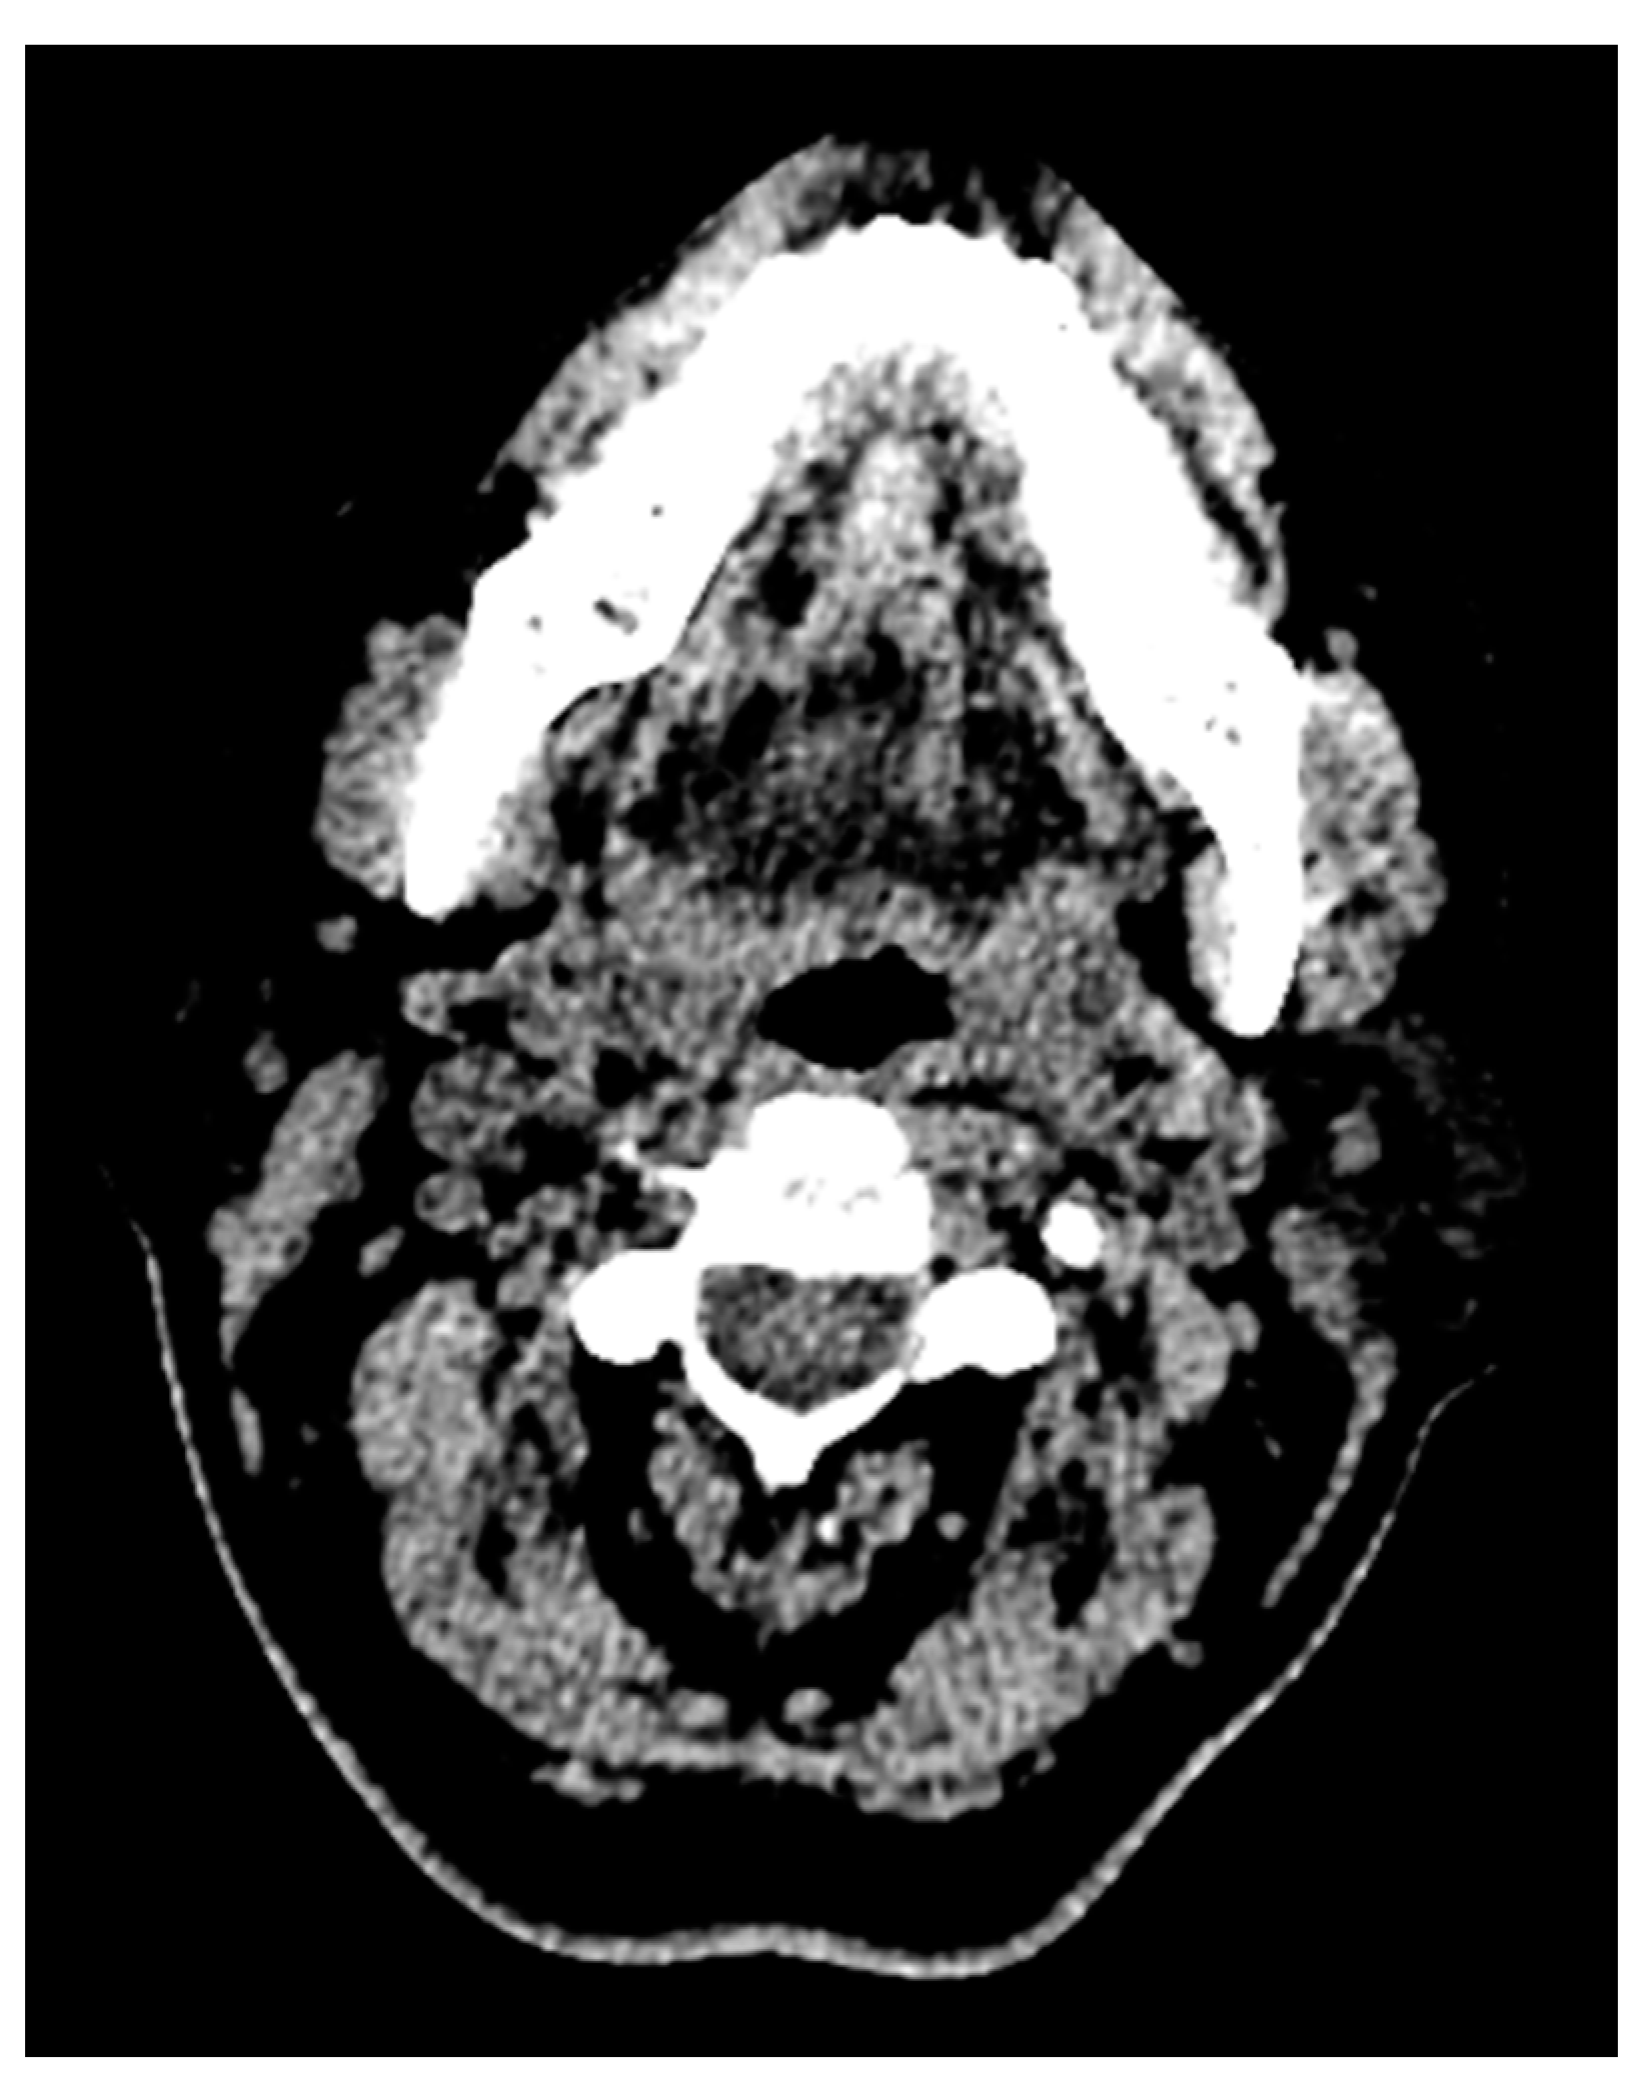

One more case of a photon starvation artifact hindering the assessment of the tongue pathology and its extent in a computed tomography image is presented in Figure 6.

This photon starvation, or quantum mottle, greatly hindered the diagnostic quality of the image. This results from insufficient X-ray photons reaching the sensor from the patient. Even though techniques such as tube current modulation (TCM) and vendor-specific and iterative reconstruction algorithms can reduce this effect, these types of artifacts still represent considerable hindrances to diagnosis and assessment.

Streak and windmill artifacts greatly affect the scan images in CT. Windmill artifacts occur due to under-sampling along the Z axis, which usually occurs in the clavicle region and the base of the skull region, where drastic anatomical changes and differential Hounsfield units are present. A black streak artifact of the beam hardening effect greatly disrupting the diagnostic quality can be seen in Figure 7.

Figure 6. Photon starvation artifact hindering the assessment of the tongue pathology and its extent in a computed tomography image.

Figure 7. Black streak artifact of beam hardening effect evident in an axial section CT image. These are usually present at the base of the skull region, where drastic anatomical changes and differential Hounsfield units are present.